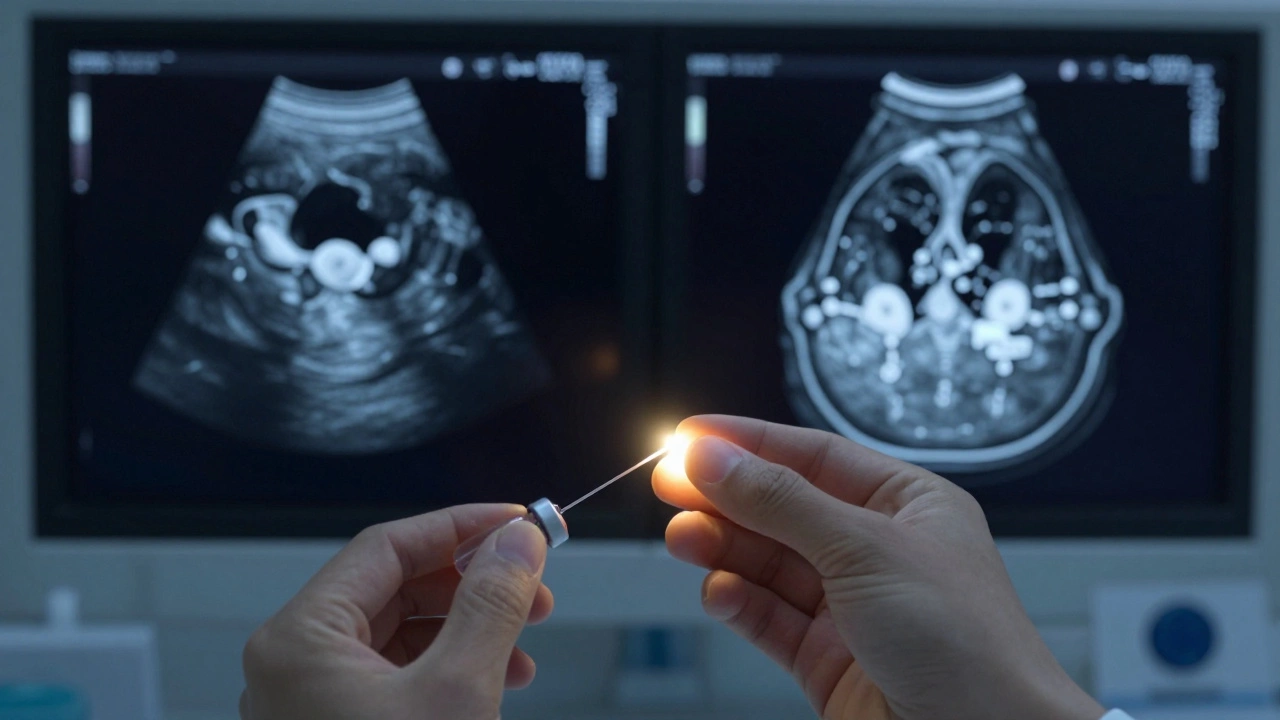

Сложная киста молочной железы на УЗИ с перегородками и кровотоком в стенке

Пункция кисты с анализом жидкости и сравнение УЗИ и МРТ